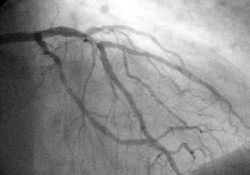

Angiography

In difficult cases or in situations where intervention to restore blood flow is appropriate, coronary angiography can be performed. A catheter is inserted into an artery (usually the femoral artery) and pushed to the vessels supplying the heart. A radio-opaque dye is administered through the catheter and a sequence of x-rays (fluoroscopy) is performed. Obstructed or narrowed arteries can be identified, and angioplasty applied as a therapeutic measure (see below). Angioplasty requires extensive skill, especially in emergency settings. It is performed by a physician trained in interventional cardiology.

Primary PCI involves performing a coronary angiogram to determine the anatomical location of the infarcting vessel, followed by balloon angioplasty (and frequently deployment of an intracoronary stent) of the thrombosed arterial segment. In some settings, an extraction catheter may be used to attempt to aspirate (remove) the thrombus prior to balloon angioplasty. While the use of intracoronary stents do not improve the short term outcomes in primary PCI, the use of stents is widespread because of the decreased rates of procedures to treat restenosis compared to balloon angioplasty.